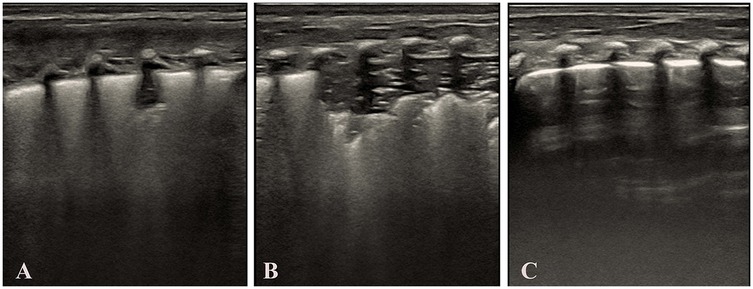

As shown in Table 5. Dose-effect trend: Complete re-expansion rates increased significantly with escalating doses [χ2_(trend) = 102.45, p < 0.001]. 1st dose: 60.00% (33/55), 2nd dose: 63.64% (14/22), 3rd dose: 75.00% (6/8). Overall success rate: 96.36% (53/55) of infants achieved complete lung re-expansion after ≤3 doses. The dose of surfactant showed a significant positive correlation with the complete re-expansion rate in NRDS infants, providing evidence-based support for individualized dosing regimens. Figure 3 illustrates sequential LUS findings in an NRDS infant.

Figure 3. Illustrates sequential LUS findings in an NRDS infant. (Panel A) Initial LUS showing pulmonary consolidation, bronchial inflation sign, absent A-lines, and irregular pleural line. (Panel B) LUS after the first dose of surfactant, showed persistent consolidation, bronchial inflation sign, absent A-lines, and irregular pleural line. (Panel C) LUS after the second dose of surfactant, showed reduced consolidation, bronchial inflation sign, absent A-lines, and irregular pleural line. (Panel D) LUS after the third dose of surfactant showed complete resolution of consolidation with a normal pleural line and visible A-lines. Images were acquired using a Mindray M9 portable color Doppler ultrasound system (Shenzhen Mindray Biomedical Electronics Co., Ltd., China).